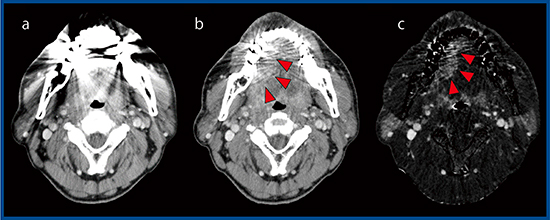

症例2は,61歳,男性の右舌縁がんである(図2)。インプラントがあるため,金属アーチファクト低減(Metal Artifact Reduction:MAR)技術の“SEMAR”(Single Energy Metal Artifact Reduction)を適用し,さらに,SURESubtractionを用いることで,腫瘍の範囲を同定できた(図2 c◀)。また,症例3は50歳,男性の舌がんである(図3)。造影MR画像では,撮像時間が長いためにモーションアーチファクトが発生し,腫瘍の同定が困難である(図3 b)。一方,SURESubtractionでは,腫瘍の辺縁も明瞭に描出され,リンパ節転移も観察できる(図3 c▶)。

図2 症例2:右舌縁がん

a:単純CT画像(SEMARなし) b:単純CT画像(SEMARあり)

c:SURESubtraction+SEMAR